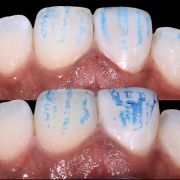

Surface texture is absloutly important to be considered. It affects light reflections on the tooth surface.

Surface texture is like the finger print of the tooth that should be replicated.